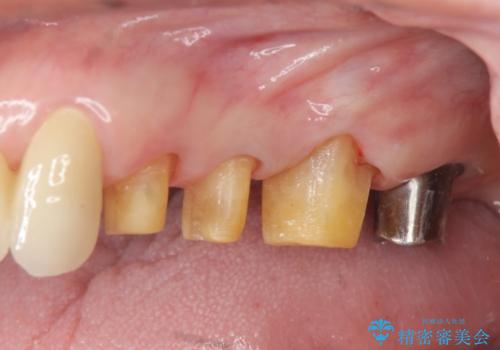

歯ぎしりに抵抗する歯周補綴 インプラント補綴

- 朝起きると歯が痛く歯ぎしり、歯の揺れの改善を求めて来院されました。

噛み合わせ・歯ぎしりにより、歯周病を発症し感染のコントロール、強い咬合力のコントロールをできるような補綴計画をたてます。

分岐部病変を併発していた歯は、抜歯としインプラントによる咬合機能の回復。残すことのできる歯は歯周治療後連結補綴を行い歯ぎしりに対抗します。

夜間のナイトガード装着は必須です。